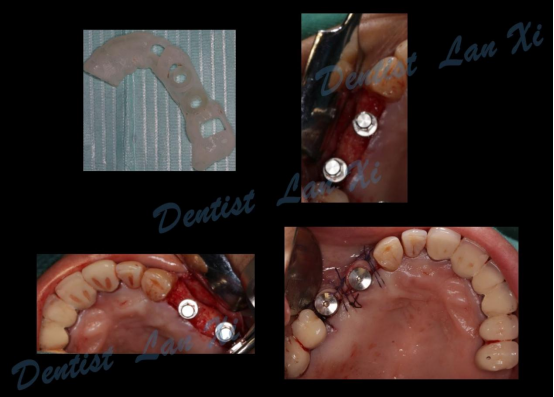

第四步:导板制作完成

(目前生成导板的方式主要有3D打印和切削两种方式)

第五步:外科手术